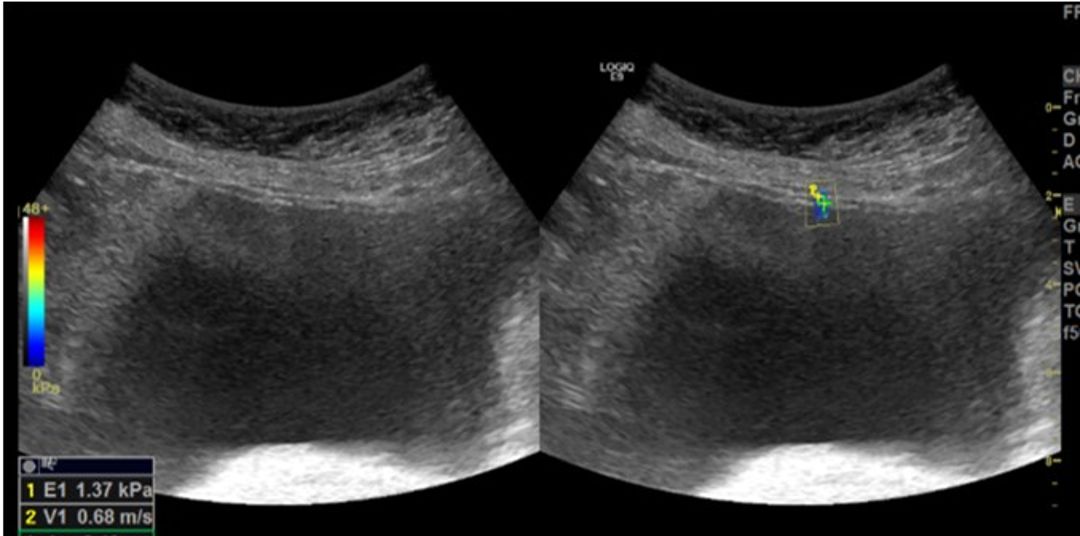

A total of 22 female patients (Group 1) aged 20 and 60 years who presented to the urology outpatient clinic with OAB symptoms between January 2024 and January 2025 and had not previously received any treatment, were included in the study. A control group of 25 healthy individuals (Group 2) without urological symptoms. Ultrasonographic parameters, age distribution, validated International Consultation on Incontinence Questionnaire-Short Form (ICIQ-SF) and, validated Overactive Bladder Questionnaire-V8 (OAB-V8) scores, bladder diaries, post-void residual urine volumes, uroflowmetry values and urinalysis results were recorded. The correlation between biomechanical parameters measured using sonoelastographic techniques and clinical diagnosis was analyzed. The measurements were taken with the patients in the supine position, ensuring that the bladder fullness was appropriate for measurement according to the patient's presentation. SWE was performed by an experienced radiologist using a Logiq E9 ultrasound device (GE Healthcare, Milwaukee, USA) with a 9L MHz probe in the B-mode plane and ARFI-based elastography with a circular 1x1 cm region of interest (ROI). Two evaluations were made from four bladder wall locations, yielding eight measurements per case. Measurements were recorded and compared between groups

Figure 3 Shear Wave Elastography (SWE) measurements of the anterior wall (White arrow) in a 58-year-old female patient